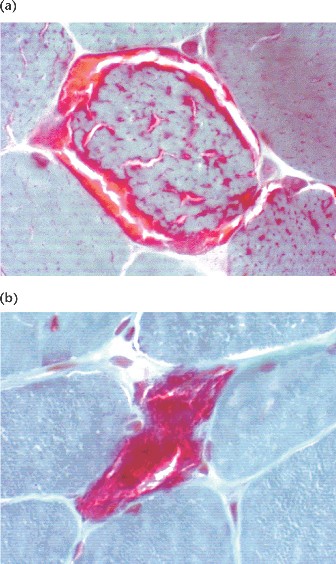

(a): The muscle fiber exhibits heteroplasmy, with mild proliferation of mutant mitochondria, showing "ragged-red" fibers when stained with dye.

(b) Marked proliferation where most mitochondria have the mutant gene.